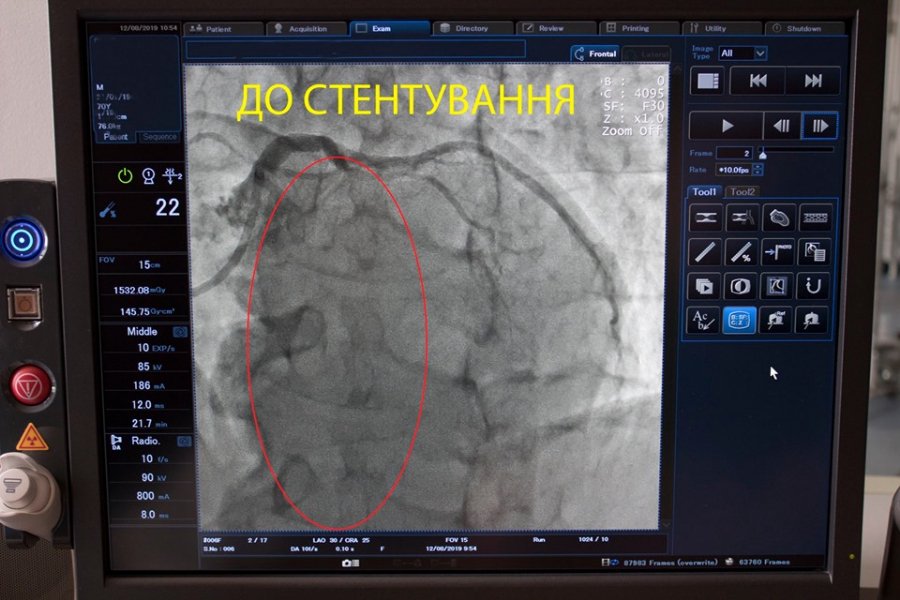

Волинські кардіохірурги Ковельського МТМО провели складну операцію зі стентування коронарної (серцевої) артерії.

"Сьогодні нашими кардіохірургами було виконано чергове стентування коронарної (серцевої) артерії пацієнту з інфарктом міокарда", - йдеться у повідомленні.

Зазначають, інфаркт виникає через припинення кровотоку до серцевого м'яза.

Відтак, стент допомагає розширити судинку та відновити циркуляцію крові.